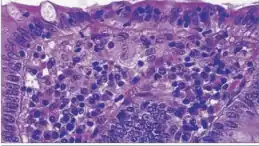

Micrograph of a colonic pseudomembrane, as may be seen in Clostridioides difficile colitis, a type of infectious colitis.

A subtype of infectious colitis is Clostridioides difficile colitis,[1] which is informally abbreviated as "C-diff colitis". It classically forms pseudomembranes and is often referred to as pseudomembranous colitis, which is its (nonspecific) histomorphologic description.